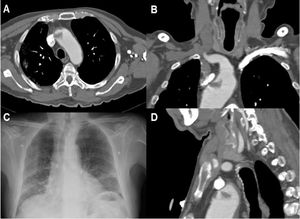

Paciente 8. A. Reconstrucción coronal de angio-TC, con un trombo endoluminal sobre placa de ateroma (flecha blanca) en la Arteria Carótida Interna Derecha (ACI). B. TAC de cráneo sin contraste, con signos de infarto cerebral en el territorio de la ACM derecha. C. angio-TC axial, trombosis aguda en ACI Derecha (flecha blanca). D. Estudio de control pasadas 4 semanas: Angio-TC axial, signos de resolución del trombo endoluminal, la placa de ateroma subyacente determinaba una estenosis residual del 30%.